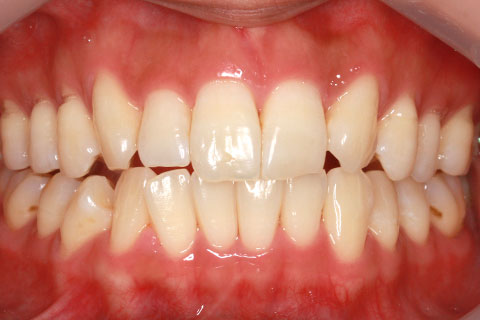

矯正期間24ヶ月

ハーフリンガル矯正3(上の歯のみ舌側矯正で治療)

治療前

治療中(開始直後)

治療中(開始半年後)

治療後

- 年齢・性別

- 25歳女性

- 治療期間

- 2年0ヶ月

- 抜歯

- 上下4番抜歯

- 治療費

- 110万円

- 備考

- 治療内容

- 施術の副作用(リスク)

- 表側矯正と比較して、力学的な操作性が複雑なため、ボーイングエフェクトを起こしやすい。